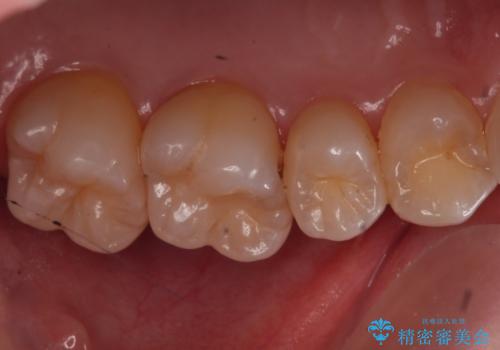

歯と歯の間の虫歯 ゴールドインレーでの修復

見た目よりも精度を優先したいとのことだったため、ゴールドインレーでの修復処置を行いました。

- 左上6 ゴールドインレー 77,000円費用は治療当時の料金となります

ゴールドの修復物は高い精度を出すことができるため非常に適合の良いものを装着することができます。